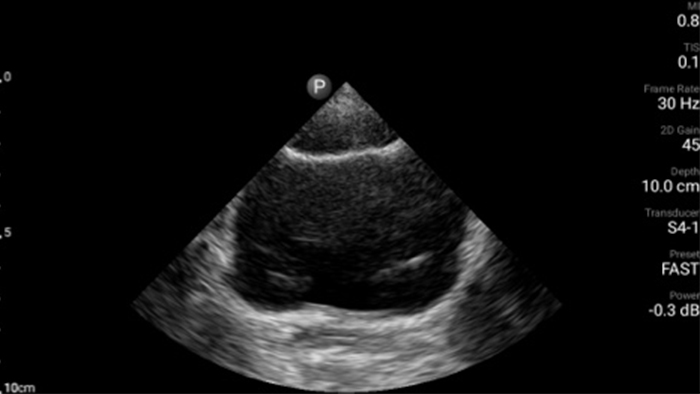

Exceptional ultrasound imaging

Lumify handheld ultrasound offers images that enhance diagnostic confidence.

See more when it counts

Lumify can help you make real-time decisions with more confidence, from assessment to recovery. Reveal the subtle details of an image, uncover enriched tissue definition with multiple angles and much more.